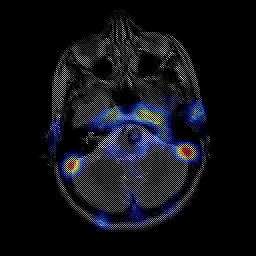

overlay -- Slice #5

[Home][Help][Clinical] Slice 5